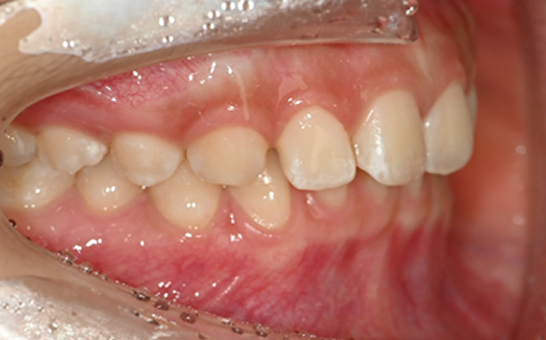

인비절라인 퍼스트(Invisalign First)는 어린이와

성장기 청소년을 위한 투명 교정 장치로, 치아와 턱뼈가

성장하는 과정에 맞춰 설계된 교정 시스템입니다.

해당하는 증상이 있다면 전문의와 상담 후 조기 교정 시

성장기 어린이에게 교합이 틀어지는것을 미리 예방 할 수 있습니다.

※ 바른선택치과의원은 의료법을 준수하며 위 케이스는 실제 내원 환자분의 동의하에 공개된 사진과 동일한 환자분께 같은 조건에서 촬영한 사진을 활용했습니다.

개인에 따라 진료 및 치료 방법이 다르게 적용할 수 있으며, 효과와 부작용이 개인마다 다르게 나타날 수 있는 점을 안내해 드리며, 진료 전 전문의료진과 충분한 상담을 권해드립니다.